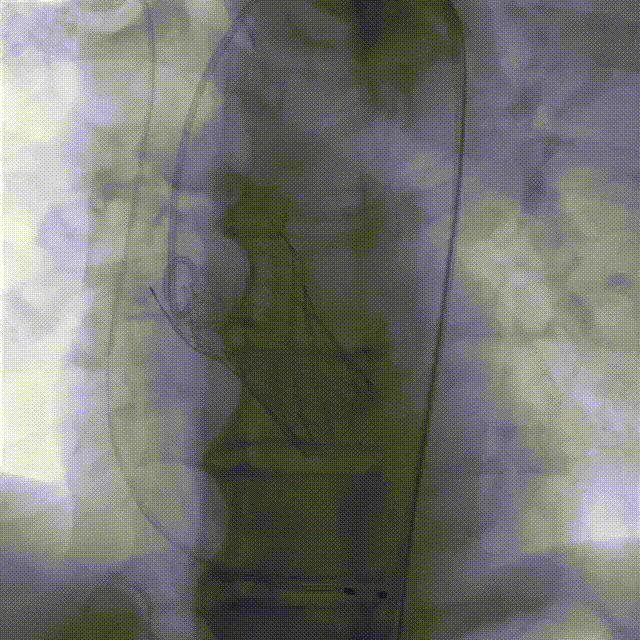

袁祖贻院长 西安交通大学第一附属医院 创新见证中国领跑,数据积累筑牢临床效果 韩克教授 西安交通大学第一附属医院 干瓣技术革新赋能特殊人群治疗,“量体裁衣”筑牢安全防线 患者病史 主诉与现病史:5年前因"血友病,血尿”就诊于当地医院,住院期间行心动超声提示主动脉瓣及二叶瓣畸形,无胸闷气短,无胸痛,咳嗽咳痰,无头晕,恶心呕吐等不适。未予以干预,后规律复查心超,3周前复查心超提示:主动脉瓣二瓣化畸形并重度狭窄,升主动脉内径明显增宽。 既往史:确诊血友病A型40年 术前超声提示:先天性主动脉瓣二叶式畸形,主动脉瓣中度狭窄,升主动脉增宽,左室舒张功能减低,EF73% 术前CT:Type0型二叶瓣,瓣叶增厚无钙化,主动脉瓣环径24.1mm,LVOT23.9mm;双侧冠脉开口高度可,窦部空间可,STJ、升主动脉内径可;预估冠脉低风险;主动脉水平夹角37.1°,主动脉弓角、弓距可;左室内径可;外周入路无明显迂曲,无钙化;双侧股动脉内径可,右侧股动脉低分叉。 手术策略 推荐右侧股动脉为主入路,左侧股动脉为辅入路。右股分叉上方1mm穿刺;仅舒张期时相,需根据球扩结果评估瓣膜尺寸,推荐使用18mm球囊进行预扩;预装AV26瓣膜。 手术过程 在右股动脉穿刺建立通路后,顺利送入大鞘。18mm球囊预扩后评估无腰无漏,后将Prostyle A® AV26瓣膜精准释放于目标位置,术后即刻造影显示无明显反流,无瓣周漏,平均跨瓣压差由术前的100mmHg降至2mmHg,患者血流动力学显著改善,术后超声证实瓣膜启闭良好。 主动脉根部造影 18球囊预扩 定位 稳定释放后脱钩 最终造影形态位置良好 外周血管造影,无血管并发症 术后超声显示无生物瓣位置固定瓣膜功能正常,无瓣周漏。 Prostyle A®预装干瓣——助力临床最优化解决方案 流入端桶状设计:流入端桶状的设计,锚定迅速,有效减少释放步骤,提升植入稳定性; 平衡的收腰设计:二叶瓣患者对瓣膜径向支撑力提出更高要求,Prostyle A®均衡的收腰设计可更好适应二叶瓣解剖,保证了EOA,有效降低了循环崩溃风险,提高瓣膜的耐久性; 预装干瓣 便捷顺安:金仕生物专利抗钙化技术运用纳米技术去除组织内的细胞碎片和磷脂,封闭游离醛基,从根本上阻断了瓣膜钙化的多项因素,显著提升了瓣膜的耐久性;同时,相比较传统戊二醛保存方式,干式存储最大限度的保留心包的亲水亲油平衡,还原组织天然曲柔性,进一步保障了瓣叶开合,保证长期耐久性。 专家简介 袁祖贻 西安交通大学第一附属医院(点击查看专家详细简历) 韩克 西安交通大学第一附属医院(点击查看专家详细简历) · END ·